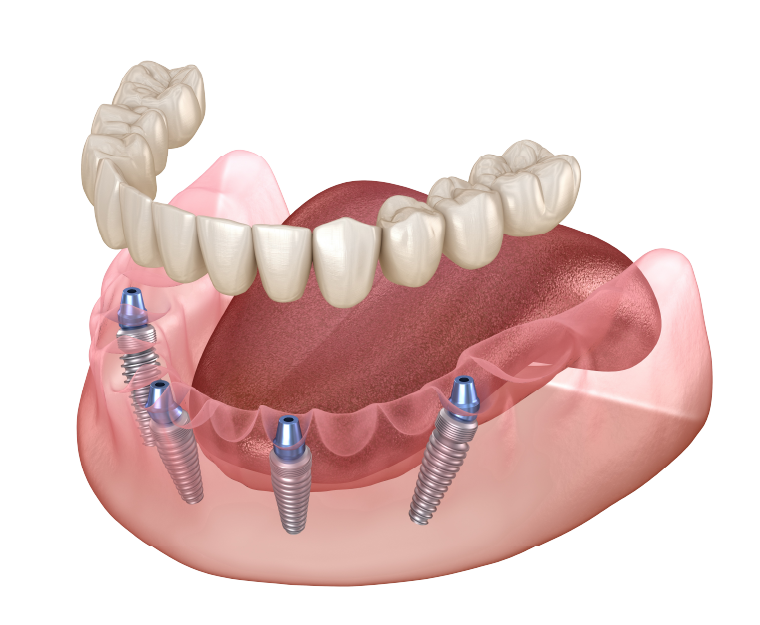

最小4本のインプラントで

片あごの歯を支えますオールオン4は、たった4本のインプラントで片顎の歯を一度に支える治療法です。

総入れ歯の違和感や痛みに悩む方、歯を多く失った方に最適で、インプラント本数が少ないため骨造成術が不要。

そのぶん身体への負担も大幅に軽減できます。 -

一方、オールオン4やオールオン6では、必要最小限の4~6本のインプラントを斜めに埋め込むことで、少ない本数でもしっかりと固定でき、従来よりも負担を大きく軽減することが可能です。